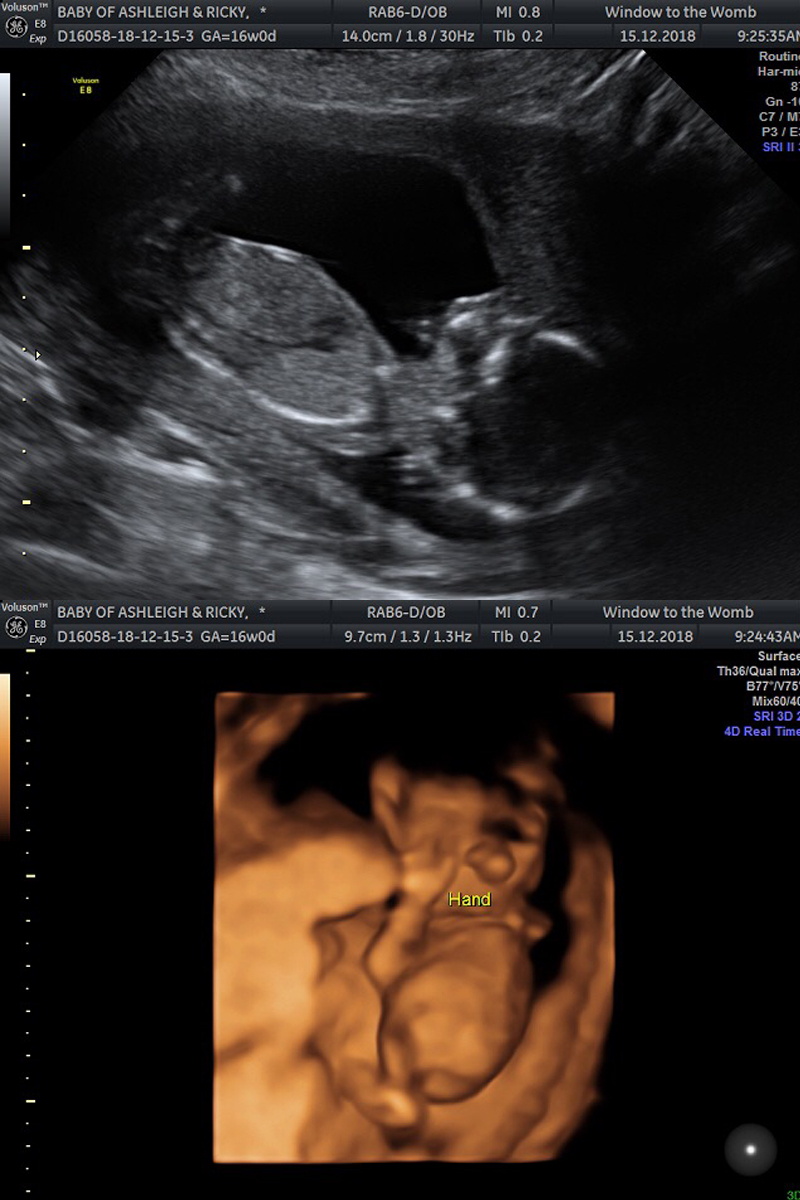

I booked a private scan for Saturday 15th December to find out the sex of our baby. It's such a personal thing whether to find out or not, but Ricky and I both agreed that we can not wait up to 42 weeks and we also wanted to better prepare ourselves with clothes, baby's room etc.

Onto the scan itself incase anyone is interested in reading more about early gender scans. We had ours at 16 weeks.

I cannot recommend Window To The Womb private clinics enough (*not sponsored). You are made to feel welcome and special the moment you walk in and the scan itself is made to be much more special in my opinion. We had the same sonographer as our early 6 week scan, so it was nice to see a familiar face and the setting is super comfortable and relaxing; spa like music and low, warm lighting and a sofa provided for up to 5 guests that you are allowed to bring.

The package we paid for gave us a gender reveal, health check and a sneak preview in 4D - something we was all really looking forward to.

Baby is a little wriggler and kept moving around, mostly standing on this head! However, these two photos are my favourite as you can really see details. In the 4D photo, it sort of looks like a huge nose, but it's actually his two hands on his face. You can see a thumb so clearly!

My beautiful boy.